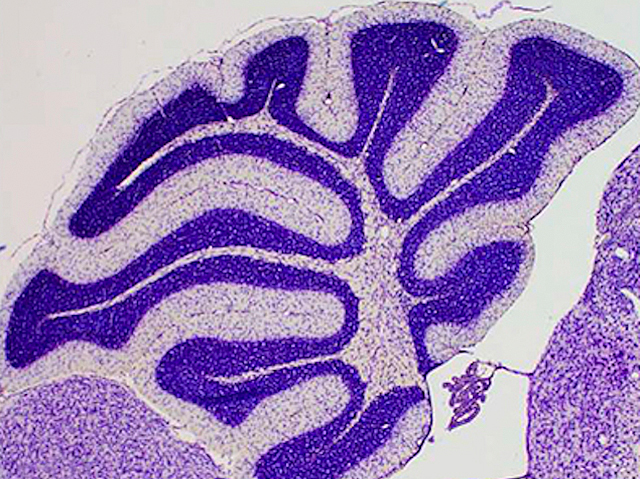

Present not Correct

Mechanisms revealed that underlie the diversity in neurological disorders related to mutations in an enzyme of the key PIP intracellular signalling pathway – potential for developing personalised therapy